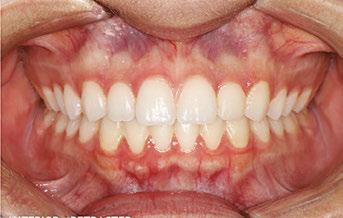

Figures 6 through 9 demonstrate a patient successfully treated with NiTime Aligners following the patient’s rejection of other systems. Figures 6 and 8 display pre- and posttreatment photos of a patient that presented with a Class II malocclusion and normal OB/OJ. This patient has teeth Nos. 7 and 10 missing congenitally. Note that the patient was treated as a child and has a canine substitution due to the missing lateral incisors. Recession was noted on tooth Nos. 2,3, 4, 5, 9, 11, 13, 14, 22, 24, 26, and 27. The patient tried labial and lingual brackets unsuccessfully, as well as a leading clear aligner to correct her malocclusion as an adult. In all three treatments, the patient could not tolerate the mechanics due to increased discomfort and was unable to complete therapy.

It is important to note that there was no refinement required for this case, and the patient finished in 26 weeks with 26 trays. Although the patient presented with significant recession, it did not worsen with treatment. As demonstrated in Figure 9, teeth aligned as planned by the OrthoFX treatment plan shown in Figure 7. Overlays of the actual results with the original treatment plan indicate a high level of predictive accuracy. Not only was a satisfactory result produced from the patient wearing the aligners, but the accuracy is quite high for the NiTime material despite the patient wearing it significantly less than the traditional 22 hours per day.

Figure 6: Class II malocclusion pretreatment

Figure 8: Class II malocclusion posttreatment. Left column pretreatment. Right column posttreatment 22 stages